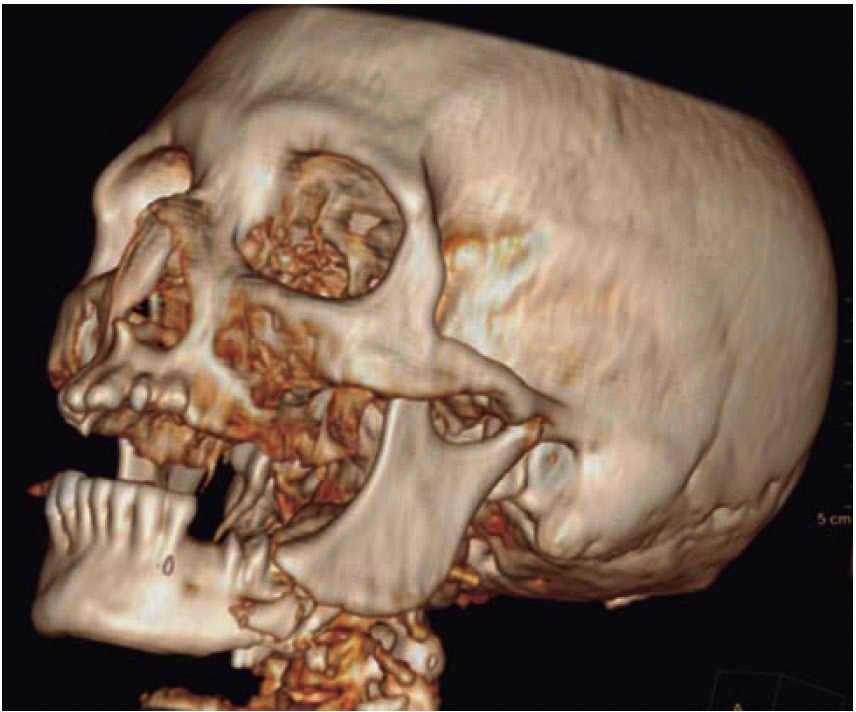

Femenino de 73 años con diagnóstico de fractura de cuerpo mandibular izquierdo por proyectil de arma de fuego (Figura 12). Paciente refiere que es asaltada en la vía pública, le retiran su vehículo y al mostrar resistencia le disparan a dos metros de distancia. Acude a nuestro hospital ocho días posteriores al evento, refiere ingresada previamente en otra casa de salud. A la exploración física presenta zona hiperémica y aumento de volumen en región submandibular izquierda fluctuante. Con orificio de entrada a nivel submandibular izquierdo con presencia de secreción blanca fétida, y orificio de salida a nivel cervical derecho cicatrizado. Intraoralmente edéntula parcial con múltiples focos sépticos en maxilar, en fondo de saco mandibular izquierdo un resto radicular de primer molar en línea de fractura. Movilidad del segmento mandibular importante por fractura de cuerpo que dificulta la deglución.

Se inicia tratamiento terapéutico de inmunización, antibioticoterapia, analgesia, extracción de focos sépticos y lavados mecánicos de la herida. La paciente no cuenta con prótesis ni parcial ni removible por lo que para establecer la relación intermaxilar y altura facial se confeccionan férulas de Gunning (Figura 13). A los diez días del tratamiento inicial se encuentra con adecuada cicatrización a nivel alveolar, con presencia de secreción no fétida a nivel de herida mandibular y se procede a realizar el segundo procedimiento mediante un abordaje extraoral con una placa de reconstrucción mandibular 2.4 y una placa 2.0 para un segmento óseo (Figuras 14 y 15). Se otorga el alta, acude a valoraciones periódicas con buena cicatrización (Figura 16), y adecuada movilidad mandibular. A las tres semanas posteriores a la reconstrucción se indica a la paciente iniciar tratamiento protésico para su rehabilitación.

Kasanjian y Converse evitaban realizar una reconstrucción inmediata por riesgo a infección, pero ese miedo se comprobó que es infundado.6,15 Por lo contrario es de gran importancia dar un manejo inicial adecuado, en especial de heridas intraorales y estabilizar las fracturas para disminuir el riesgo o como parte de la resolución en complicaciones infecciosas. Cunningham y cols. recomiendan una actitud más conservadora realizando el tratamiento en varias fases en casos de contaminación severa, malas condiciones sistémicas que pueden fracasar la reconstrucción primaria.9,16 León y cols. consideran ideal realizar un manejo inicial y esperar para el tratamiento de fracturas entre 6 y 18 días. Este tiempo permite controlar la infección, disminuye el edema, congestión venosa, y una mejoría de la circulación microvascular.7 Nosotros consideramos que hacer un tratamiento inicial complejo en un sólo tiempo es viable al encontrarse el paciente en un centro especializado de trauma, con personal multidisciplinario que trata estos casos de forma frecuente. En nuestro caso, la atención es en un hospital general donde la incidencia de este tipo de problemas no es tan común, por lo que decidimos hacerlos en dos tiempos quirúrgicos cuando el defecto es grande o se presenta una infección como complicación de por medio. En acuerdo con varios autores, 14,21 damos énfasis en la necesidad de un estudio tipo cone-beam o topográfico axial para determinar el daño en los tejidos duros y la ubicación del proyectil cuando no presenta orificio de salida. Todo paciente con herida por arma de fuego debe atenderse en un centro de trauma de manera multidisciplinaria.

En los tres casos presentados se inicia con valoración cardiopulmonar, manejo de vía aérea, control hemodinámico, ventilación, discapacidad neurológica y daños específicos.9-11 Con la exploración física determinamos la extensión de daño en los tejidos, presencia de orificios de entrada y salida para descartar la presencia de bala al interior en una cavidad o tejido (caso 2). El manejo maxilofacial se inicia con desbridaje conservador, lavado, extracción de restos radiculares, sutura y estabilización oclusal. La reducción y fijación de las fracturas (caso 1 y 3) se realizó en un segundo acto quirúrgico con placas de reconstrucción. En los casos expuestos se observó una buena evolución, una cicatriz ósea favorable y la necesidad de continuar con una rehabilitación oral mediante prótesis o implantes osteointegrados. Las complicaciones y secuelas son comunes y surgen por lo general a causa de la severidad de las lesiones iniciales, retraso en el tratamiento por riesgo vital o estado sistémico del paciente.